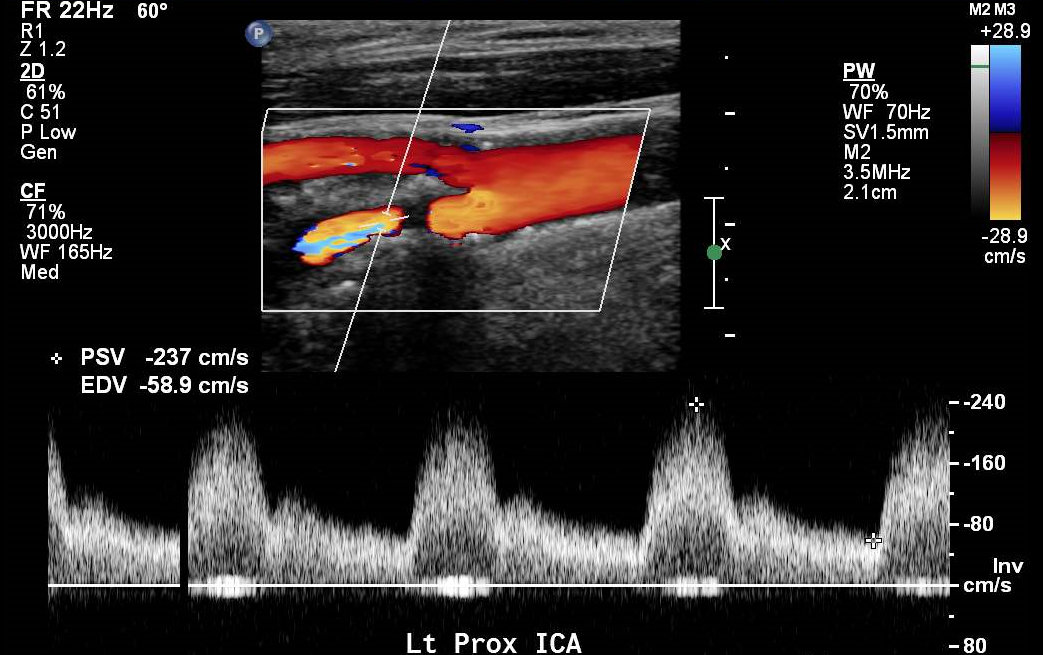

Carotid Duplex - ICA Stenosis

-